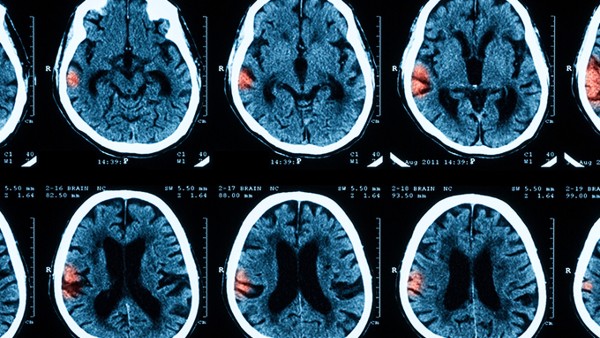

脑梗塞临床又称缺血性中风,局部脑组织地区供血障碍,缺血缺氧的病理变化和脑组织坏死,产生相应神经功能不足的临床表现等因素可能引起脑梗塞。根据发病因素不同,脑梗塞可分为脑血栓、脑栓塞、腔隙性脑梗塞等。其中,脑血栓是常见的脑梗塞类型,约占所有脑梗塞的60%。